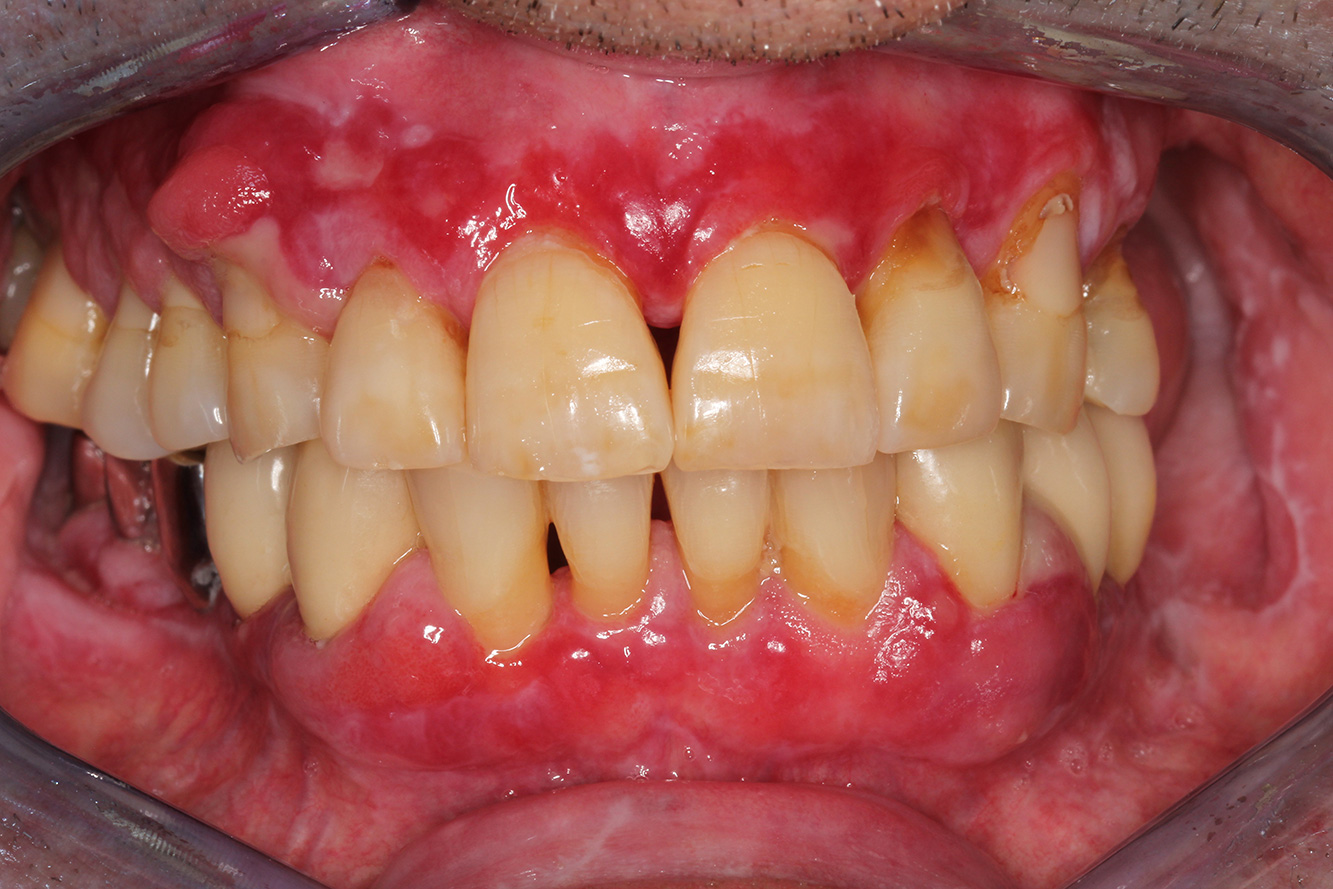

A 71-year old patient presents with having previously undergone a kidney transplant and with a history of hypertonia (high blood pressure). Due to his medical history, long-term medication with cyclosporine is required to suppress the immune system, as well as amlodipine to lower blood pressure. The patient also reports sensitive and bleeding gums. From an oral health perspective, the patient has undergone dental restoration and has eight missing teeth, pronounced gingival growth, and grade B, stage II periodontitis with active pockets and initial root caries on tooth 22. The caries risk assessment determines a moderate risk of caries (API 60). The following treatment recommendations can be determined for the prophylaxis session.

Based on the patient’s medical history, it is possible to identify a particular risk of complications. Due to the kidney transplant, the patient is immunosuppressed (cyclosporine), and therefore has a weakened immune system and requires infection prophylaxis (recommendation: 2 g of amoxicillin as an antibiotic, 1 hour before the session). At the same time, the patient’s long-term medication carries an increased risk of disease, as the gingival overgrowths identified are associated with this medication (20).

The patient’s situation must be addressed, especially when it comes to motivation and instruction. Due to the gingival overgrowths, the patient finds it difficult to practise good oral hygiene at home. The increased susceptibility to infection as well as the progression and emergence of the overgrowths (22) should be discussed at the patient’s level. At the same time, the patient should be instructed in hygiene techniques that are tailored to his individual needs.

A shorter recall interval of three to four months is recommended for this patient. This is mainly due to the gingival overgrowths associated with the patient’s medication, the fact these overgrowths make at-home oral care difficult for the patient, and the risk of progression of periodontitis.